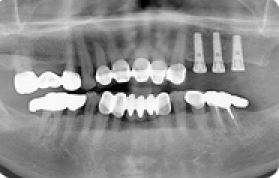

| 8 |

|

임플란트 상악동거상술 전후사례 | 2020.03.06 |